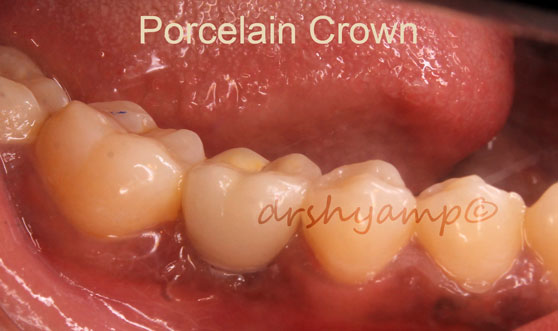

single molar dental implant

single molar dental implant

single molar dental implant

single molar dental implant

single molar dental implant

single molar dental implant

single molar dental implant

single molar dental implant

single molar dental implant

single molar dental implant

single molar dental implant

single molar dental implant

single molar dental implant

single molar dental implant

single molar dental implant